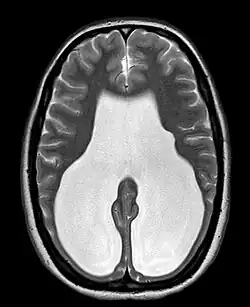

Colpocephaly is characterized by disproportionately large occipital horns of the lateral ventricles (also frontal and temporal ventricles in some cases). MRI and CT scans of patients demonstrate abnormally thick gray matter with thin poorly myelinated white matter. This happens as a result of partial or complete absence of the corpus callosum. Corpus callosum is the band of white matter connecting the two cerebral hemispheres. The corpus callosum plays an extremely important role in interhemispheric communication, thus lack of or absence of these neural fibers results in a number of disabilities.[12]

After birth, MR imaging can be done to look for cephalic abnormalities. This is the most commonly used method for diagnosing colpocephaly. Physicians look for abnormally large occipital horns of the lateral ventricles and diminished thickness of white matter.[12] Spinal tapping is not a preferred method for diagnosis because newborn babies with colpocephaly or hydrocephaly have open fontanelles which makes it difficult to collect CSF. Also, colpocephaly is not associated with increased pressure.[13]